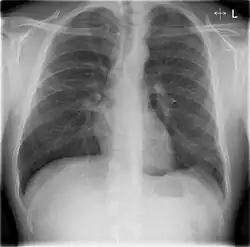

Chest X-rays and X-ray computed tomography (CT) can reveal areas of opacity (seen as white), indicating consolidation.[14] CAP does not always appear on x-rays, sometimes because the disease is in its initial stages or involves a part of the lung not clearly visible on x-ray. In some cases, chest CT can reveal pneumonia not seen on x-rays. However, congestive heart failure or other types of lung damage can mimic CAP on x-ray.[16]

Chest X-rays of a CAP patient before (left) and after treatment

CAP is treated with an antibiotic that kills the infecting microorganism; treatment also aims at managing complications. If the causative microorganism is unidentified, which is often the case, the laboratory identifies the most effective antibiotic; this may take several days.